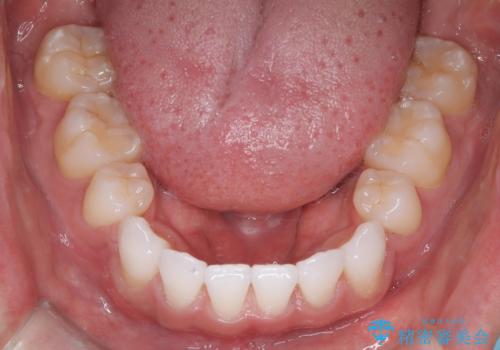

前歯の突出を防ぎながらガタつきを解消。上下左右4番抜歯による審美ワイヤー矯正

治療完了後、重なり合っていた歯はきれいに整い、懸念されていた前歯の突出も一切起こることなく、理想的な噛み合わせを実現しました。装置が目立ちにくかったため、治療期間中も周囲の目を気にすることなく、前向きに治療に取り組んでいただくことができました。